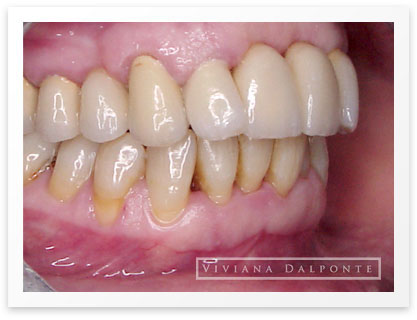

CASO 6: Restauración con prótesis fija en ambos maxilares